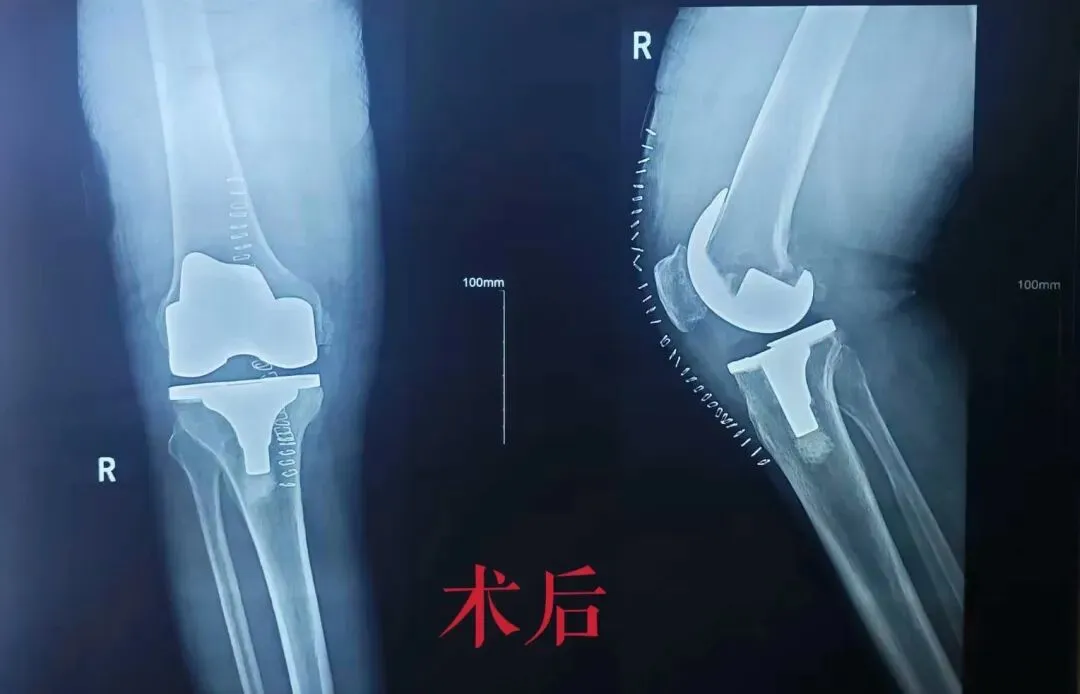

右膝表面置换术——不换整条腿,只换"关节面"

磨掉坏的软骨 → 装上金属+假体 → 矫正力线

精准术前规划🌱

• 基于MRI三维重建,定制个体化截骨方案

• 矫正15°内翻畸形,恢复下肢力线(避免"O型腿"复发)

术前术后对比/ 骨科

术前     术后

走路像针扎 → 基本无痛

蹲不下   → 能蹲能爬楼

O型腿   → 腿变直了